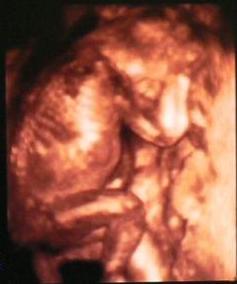

Apa csinált a 4D UH-ról képet. Persze nem a legtökéletesebb a felbontás, de megpróbálom feltenni.

Kép MiniManó